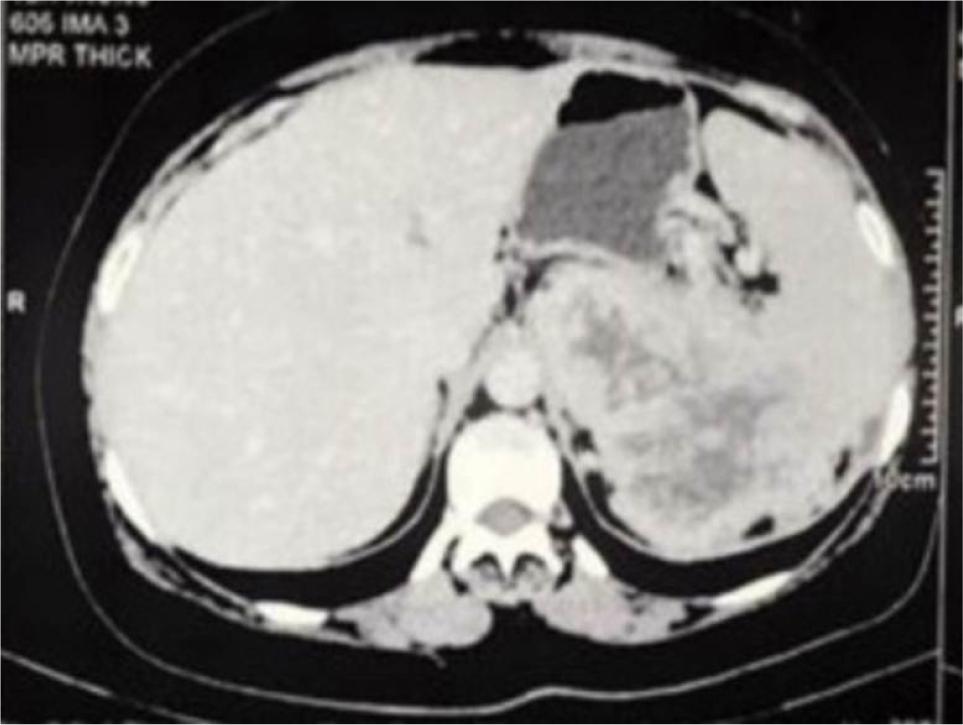

A 50-year-old man presented with left loin pain. An ultrasound, followed by a CT scan, revealed a 17.5 cm left renal mass invading the left suprarenal gland, spleen, pancreatic tail, and a part of the diaphragm. He had excellent performance status and no distant metastases. Radical nephrectomy through chevron incision under epidural block with general anesthesia was performed. Over a 2-hour operation, the entire mass was removed including the kidney, adrenal gland, spleen, pancreatic tail, and diaphragmatic fibers. There was a large chain of para-aortic lymph nodes that was removed as well. The estimated blood loss was 300 mL, and no blood transfusions were required. Chest tube was inserted and removed after 48 h. Histological examination revealed Grade 4 clear cell RCC with extension into the spleen, pancreatic tail, and diaphragmatic fibers. Invasion of main renal vein and pelvicalyceal system was identified. There was neither sarcomatoid differentiation nor lymphovascular invasion. All surgical margins were negative. The resected lymph nodes were reactive with no evidence for cancer (Stage T4N0). Preoperatively, Hgb was 12 g/dL and eGFR was 85 mmol/L. On the first postoperative day, Hgb was 10 g/dL and eGFR dropped to 60 mmol/L, and these values were nearly stable during hospital admission. Four weeks post operation, the patient was reviewed. His wound had healed well, with no complications. Chest X-ray was normal. Hgb did rise to 13 g/dL, and eGFR was 80 mmol/L. The patient was discharged after a 3-day uneventful hospital stay. Six months’ CT scan did not show any evidence for cancer recurrence. We referred the patient to medical oncology team, and we agreed on surveillance, and systemic therapy was not offered. Within that short term follow-up, the patient recovered well and did not show evidence for residual or recurrent cancer. Patient’s consent was obtained for data collection and publication. Ethical approval was not required. Figure 1 is a CT section showing the advanced renal mass and Figure 2 is an operative image for the resected kidney, spleen and pancreatic tail.

Figure 1: Axial CT abdomen showing large left renal mass infiltrating the spleen and pancreas.